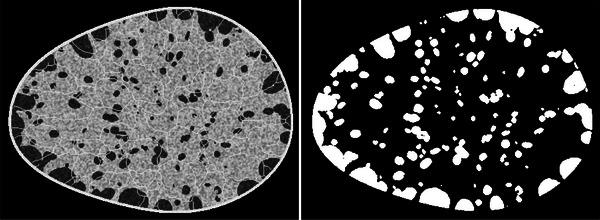

As part of this Grand Challenge, a common training dataset and an evaluation procedure was developed for benchmarking deep generative models for medical image synthesis. To create the training dataset, an established 3D virtual breast phantom was adapted. The resulting dataset comprised about 108 000 images of size 512   512. For the evaluation of submissions to the Challenge, an ensemble of 10 000 DGM-generated images from each submission was employed. The evaluation procedure consisted of two stages. In the first stage, a preliminary check for memorization and image quality (via the Fréchet Inception Distance [FID]) was performed. Submissions that passed the first stage were then evaluated for the reproducibility of image statistics corresponding to several feature families including texture, morphology, image moments, fractal statistics, and skeleton statistics. A summary measure in this feature space was employed to rank the submissions. Additional analyses of submissions was performed to assess DGM performance specific to individual feature families, the four classes in the training data, and also to identify various artifacts.

作为本次大挑战的一部分,开发了一个通用训练数据集和一个评估程序,用于对医学图像合成的深度生成模型进行基准测试。为了创建训练数据集,对一个已建立的3D虚拟乳房模型进行了改编。生成的数据集包含约108000张大小为512×512的图像。为了评估挑战赛的参赛作品,使用了来自每个参赛作品的10000张由深度生成模型生成的图像组成的集合。评估程序包括两个阶段。在第一阶段,进行了记忆和图像质量的初步检查(通过弗雷歇因距离 [FID])。通过第一阶段的参赛作品随后被评估与包括纹理、形态、图像矩、分形统计和骨架统计在内的几个特征族对应的图像统计数据的可重复性。在这个特征空间中使用一个汇总度量对参赛作品进行排名。对参赛作品进行了额外分析,以评估特定于各个特征族、训练数据中的四个类别的深度生成模型性能,还识别各种伪像。